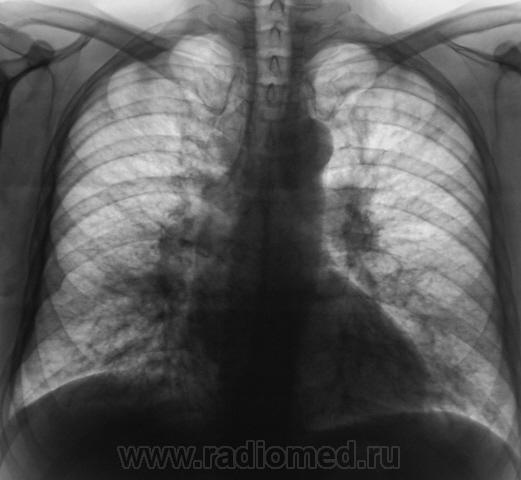

Через 10 дней, после интенсивнейшей противовоспалительной терапии пациент направлен на рентген-контроль.

Ух крррасоттища то - Прям - брокколи или цветная капуста какая то..

Я склоняюсь к сердечным делам - если был застой - получили отек.

у нас часто капают а за диурезом не следят.

Пациенту ничего не капали. Сейчас, пациент в областной "конторе" - ОПТД.

Это туберкулез? Возможно, но кроме противовоспалительной терапии нужно сердечку помочь.